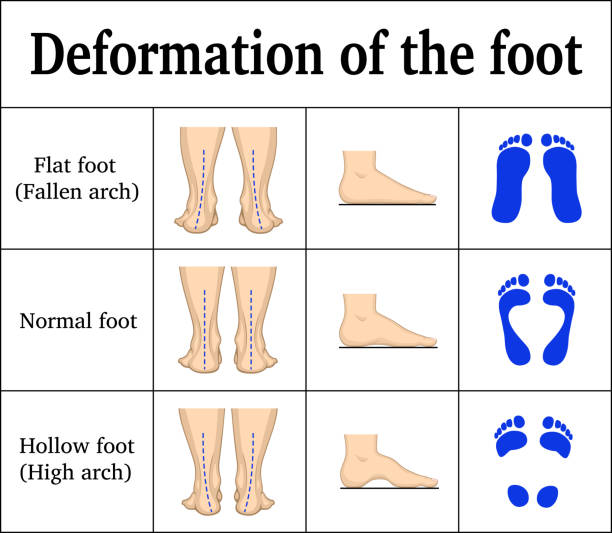

Flat Feet

Flatfeet is a common condition, in which the arches on the inside of the feet flatten when pressure is put on them. When people with flatfeet stand up, the feet point outward, and the entire soles of the feet fall and touch the floor.

Most people have no symptoms associated with flatfeet. But some people with flatfeet experience foot pain, particularly in the heel or arch area. Pain may worsen with activity. Swelling may occur along the inside of the ankle. There may also be complaints of heel, lower leg, knee, hip, and/or back pain.

People without flatfeet can also develop the condition. Arches can collapse abruptly after an injury. Or the collapse can happen over years of wear and tear. Over time, the tendon that runs along the inside of the ankle and helps support the arch can get weakened or tear. As the severity increases, arthritis may develop in the foot.

High arched feet

Pes cavus is a foot with an abnormally high plantar longitudinal arch. People who have this condition will place too much weight and stress on the ball and heel of the foot while standing or walking. Children with cavus foot also experience frequent ankle sprains, since high arches cause the ankle to naturally roll outward.

While cavus foot deformity varies in severity from a subtle and flexible to a severe and fixed deformity, careful assessment is required to identify and prescribe the correct pes cavus treatment.